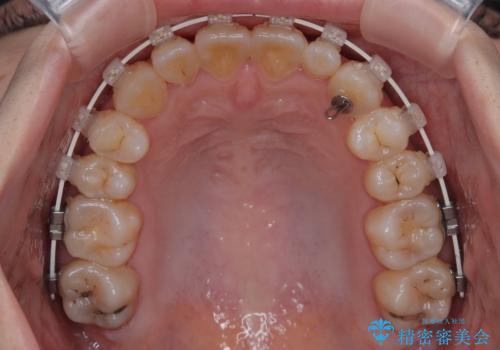

- 矯正装置

- 審美装置

診査の結果、上下顎ともに叢生が認められましたが、ワイヤー矯正・マウスピース矯正のいずれでも対応可能な症例でした。

という患者様のご希望を踏まえ、プラスチックブラケット+コーティングワイヤーを用いたワイヤー矯正を選択しました。

金属色が目立ちにくく審美性が高い

確実に歯を動かせるため治療計画が立てやすい